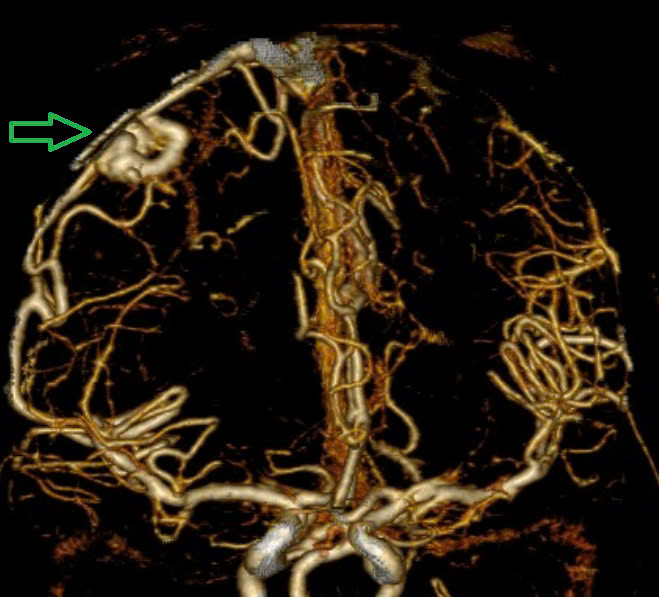

Kết quả chụp MSCT mạch não cho thấy chảy máu não thuỳ đỉnh phải, chảy máu não thất do vỡ AVM ( điểm Spetzler Martin 2 điểm). Bệnh nhân đã được phẫu thuật lấy máu tụ và khối dị dạng. Tuy được điều trị tích cực nhưng di chứng để lại vô cùng nặng nề. Sau một tháng điều trị, bệnh nhân chưa nhận thức được, liệt hoàn toàn nửa người trái…

| Hình ảnh chụp MSCT mạch não: Chảy máu não thuỳ đỉnh phải, chảy máu não thất do vỡ AVM ( điểm Spetzler Martin 2 điểm) của bệnh nhân nữ, 29 tuổi. |